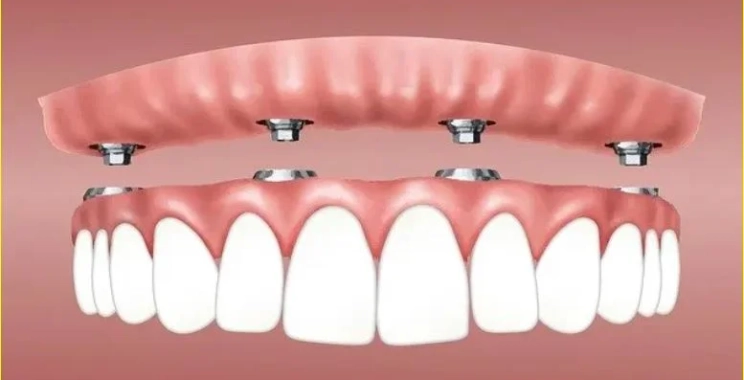

عمليات زراعة الفك أو كما هي معروفة All on 4 هي واحدة من أحدث التقنيات في طب الأسنان خلال الآونة الأخيرة، حيث يقوم الطبيب بزراعة طقم أسنان للفك بالكامل ويتم تثبيته عن طريق 4 غرسات وهي تختلف عن الطريقة التقليدية لزراعة الأسنان من قبل، علاوة على ذلك فهي أفضل بديل للأشخاص الذين فقدوا أسنانهم بالكامل.

هناك بعض المراحل التي يتبعها الطبيب عند زراعة الفك الكامل لكي يتم تثبيتها بالشكل الصحيح لها، وجاءت هذه المراحل كما يلي:

- وضع الغرس السنية داخل عظام الفك ثم القيام بخياطة أنسجة اللثة.

- بعد مرور شهرين والتئام عظم الفك جيدا حول الغرس السنية يبدأ بتركيب الدعامة الخاصة بالغرس المعدنية ثم وضع الأسنان الصناعية.